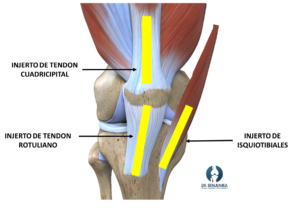

Como norma general, el injerto autólogo será más resistente y será capaz de reintegrarse antes en la rodilla. Los tipos más frecuentes de injertos empleados para la reconstrucción del ligamento cruzado anterior son:

Tipos de injerto

Tendón rotuliano o Hueso tendón Hueso (HTH): Se ha considerado el más resistente históricamente, por lo que es la técnica más empleada en Estados Unidos, y suele ser el más empleado en deportistas profesionales. Como ventaja destaca la resistencia del injerto, aunque su inconveniente principal es que el paciente puede experimentar molestias en la región anterior de rodilla tras la cirugía.

Tendón cuadricipital: Tiene una resistencia similar al HTH, su principal ventaja es que la recuperación inicial puede ser más rápida y con menor dolor de rodilla que el HTH.

Tendones isquiotibiales: En España es el más empleado, es la más rápida de obtener, y ofrece una buena resistencia. Sus principales problemas son que se puede lesionar el nervio sural al obtenerlo (1% de los casos) y se puede notar pérdida de fuerza al subir escaleras o cuestas.